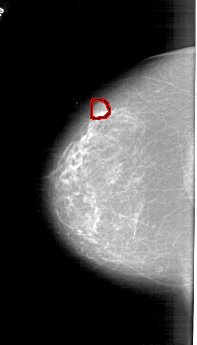

FILE: A_1778_1.LEFT_CC.OVERLAY

TOTAL_ABNORMALITIES 1

ABNORMALITY 1

LESION_TYPE MASS SHAPE LOBULATED MARGINS CIRCUMSCRIBED

ASSESSMENT 4

SUBTLETY 5

PATHOLOGY BENIGN

TOTAL_OUTLINES 1

BOUNDARY